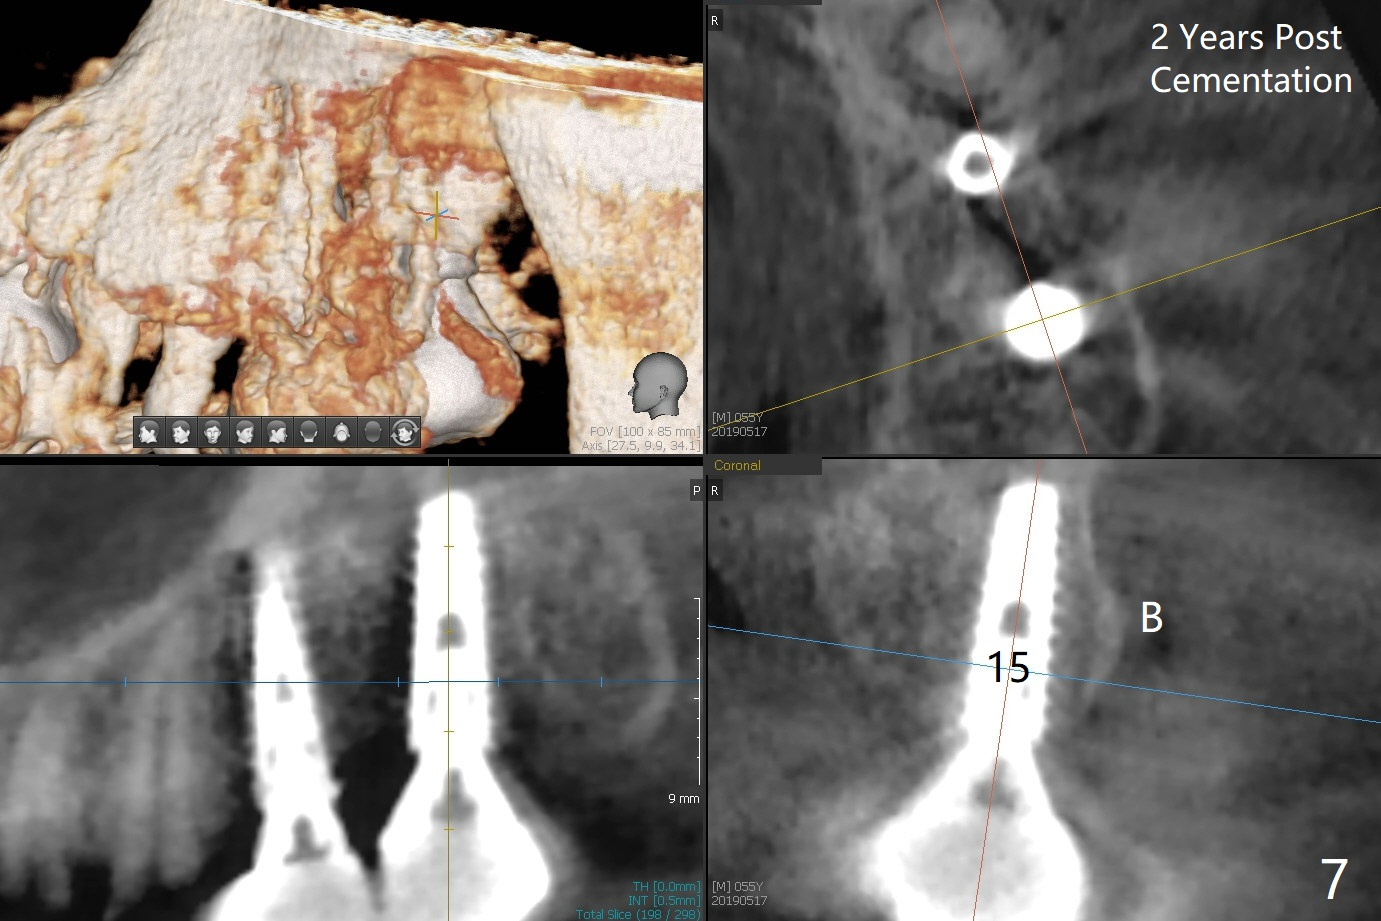

As shown by CT, the ridge at #14 is narrower than that of #15 (confirmed after incision), whereas the density at #14 is higher than that of #15. The osteotomies are established by combination of magic osteotomes and drills after change in trajectory (Fig.1-3). Following placement of 4.5x13 and 5x13 mm IBS implants and 6x4(3) and 6.5x4(3) mm pair abutments at #14 and 15 (Fig.4), flaps are sutured for hemostasis. Since the patient does not tolerate the surgery too well (unstable hypertension and oozing), immediate provisional is delayed. Periodontal dressing is applied instead. While the implants are healing, porcelain chips at the upper anterior bridge. There appears no bone resorption 6 months postop (Fig.5). Impression is taken following changing abutment to 5x4(2) mm at #14 and Diode gingivectomy. A panoramic film is taken 1 year 2 months post cementation. CT taken 2 years post cementation shows relatively good trajectory of these 2 implants (Fig.6,7).